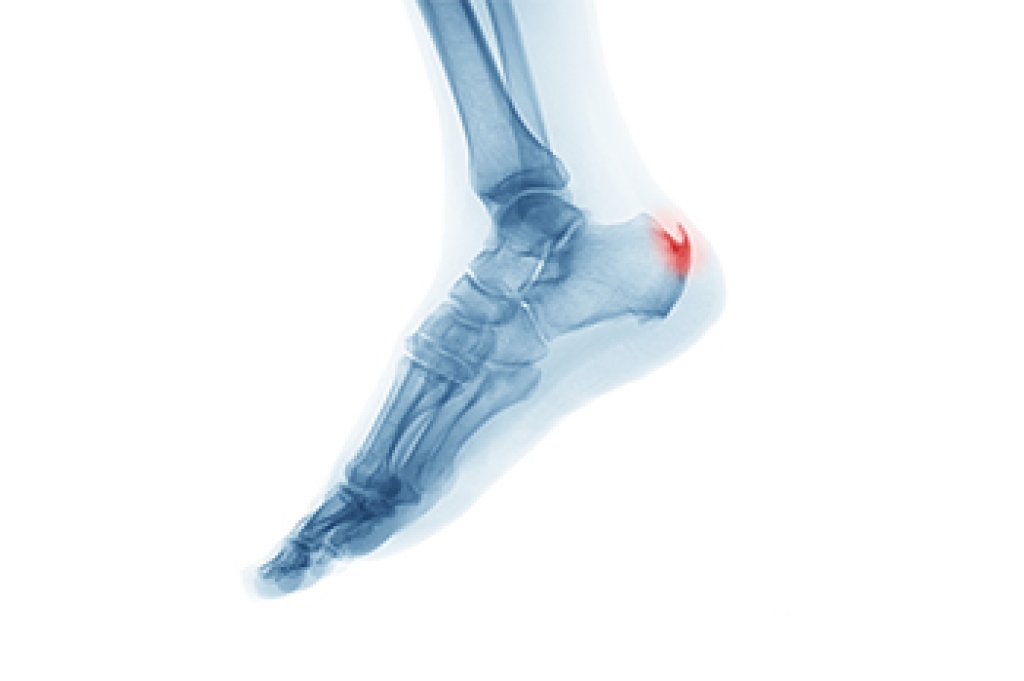

Cuboid syndrome occurs when the small cuboid bone on the outer side of the mid-foot shifts slightly out of position or becomes irritated, leading to sharp or aching discomfort. It is seen most often in active individuals, including dancers, runners, and people who spend long periods of time on their feet, because repetitive motion and sudden twists can place extra stress on the outer foot. Others may develop it after an ankle sprain, as the injury can disrupt normal alignment. Symptoms include pain along the outer mid-foot, difficulty pushing off during walking, tenderness when pressing the area, and a feeling of weakness or instability. Treatment focuses on restoring alignment, reducing irritation, and supporting the foot as it heals. A podiatrist can perform targeted manipulation, provide taping or padding, and recommend footwear or inserts that improve stability. If outer foot pain continues to interfere with movement, it is suggested that you see a podiatrist who can accurately diagnose and treat cuboid syndrome.

Cuboid syndrome is a common cause of lateral foot pain, which is pain on the outside of the foot. The condition may happen suddenly due to an ankle sprain, or it may develop slowly overtime from repetitive tension through the bone and surrounding structures.

A common symptom of cuboid syndrome is pain along the outside of the foot which can be felt in the ankle and toes. This pain may create walking difficulties and may cause those with the condition to walk with a limp.